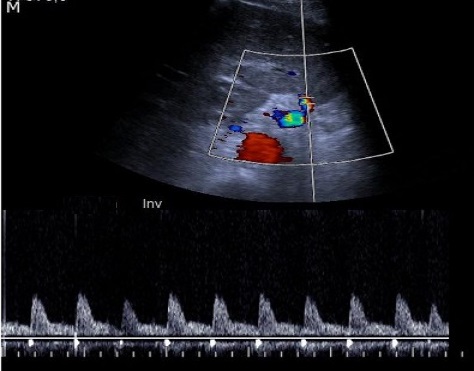

Par la technique echographie en Doppler

difference de sa pulse |

Image echograpghique de

normalement variée entre 9 -10mm |

La forme des ondes de pulse de

splenique est souvent monophasique |